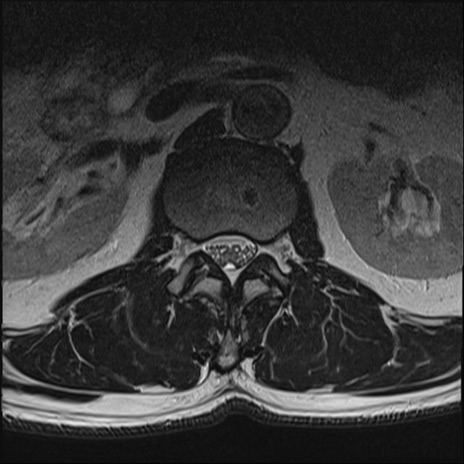

【整形】TIPS症例2 腰椎MRI T2WI(横断像)

【症例】70歳代男性

【主訴】左下肢痛

【現病歴】2週間前くらいから腰痛、左下肢痛あり。左臀部から大腿、下腿外側のしびれが常時ある。歩行とともに同部位の痛みあり。

【身体所見】Lasegue70-/60+、Bragard-/±、PTR ±/±、ATR -/-、IP 5/5、TA 5/4、TS 5/5、EHL 右第1足趾なし/3、FHL 5/5、hypersthesia(-)、足背動脈触知良好

異常所見と診断は?